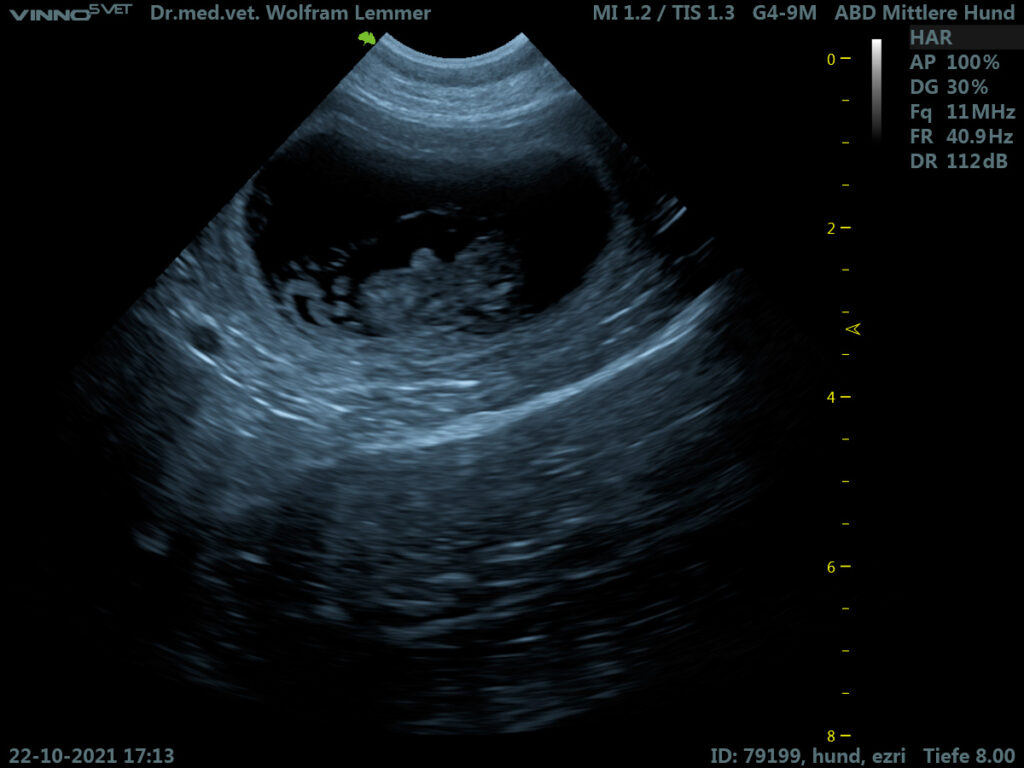

Die Ultraschalluntersuchung am 22. Oktober zeigte mehrere gutentwickelte Föten, die in ihren Fruchtblasen hüpften. Die kleinen Herzchen schlagen zu sehen, ist immer wieder ein ergreifender Moment.